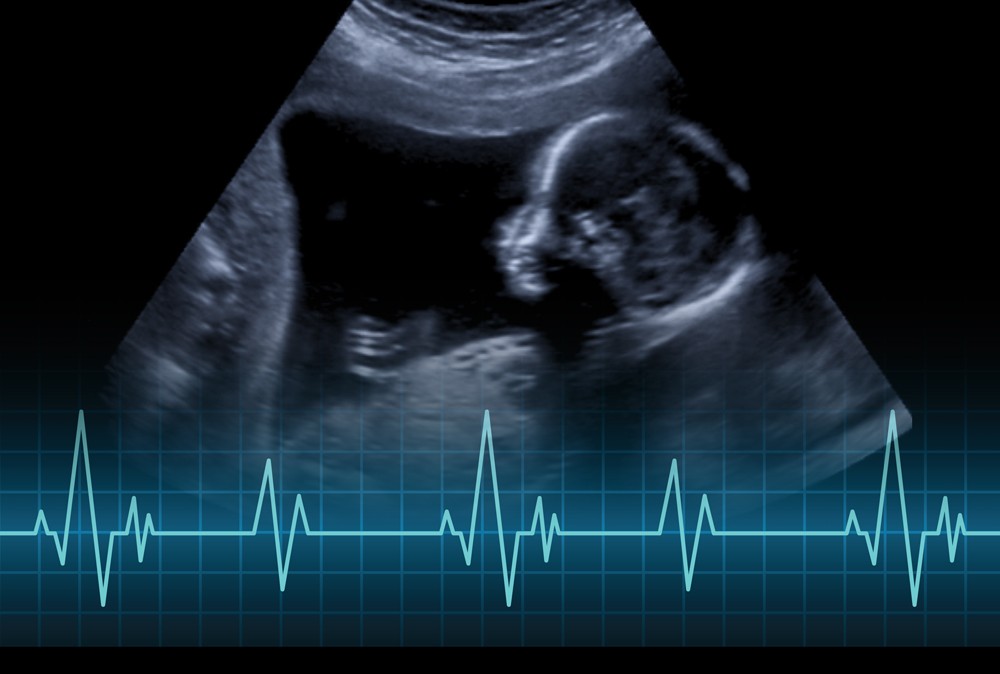

(Hoboken, N.J. – Aug. 7, 2019) – The thump, thump of a baby’s heartbeat is a milestone in any pregnancy. Now, researchers at Stevens Institute of Technology have developed a technique that could allow expectant parents to hear their baby’s heartbeat continuously at home with a non-invasive and safe device that is potentially more accurate than any fetal heartrate monitor currently available in the market.

The device, which uses the same commercial sensors used in smartphones to horizontally or vertically orient the device, can record vibrations sent through a mother’s abdomen when her baby’s heart beats or when the fetus squirms and kicks. Lauded by physicians, the device could potentially reduce an estimated 2.6 million stillbirths per year worldwide.

Many stillbirths are preceded by variations in fetal movement and heartrate, so affordable, lightweight monitors that detect vibrations generated from a heartbeat could be worn continuously in the final weeks of pregnancy to ensure that distressed fetuses receive prompt medical attention. The work is reported in the July 24 early access issue of IEEE Sensors Journal.